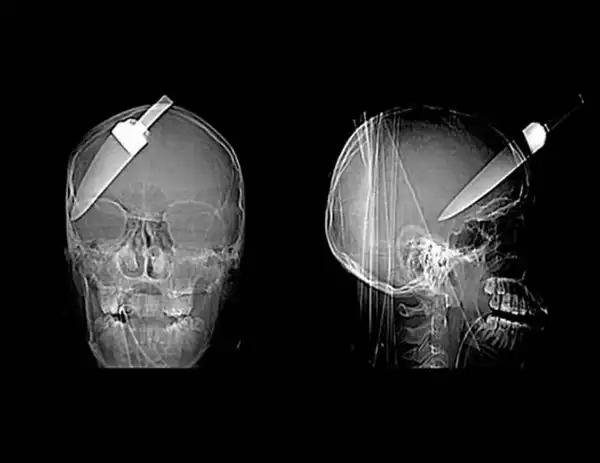

Гвоздь в человеческом черепе – пациент случайно выстрелил в себя из пневматического молотка. Он даже не понял, что выстрелил в себя – 10-сантиметровый гвоздь обнаружили только через 6 дней.

Нож в голове 10-летнего мальчика. Мальчик выжил.

12-сантиметровый нож в черепе подростка.